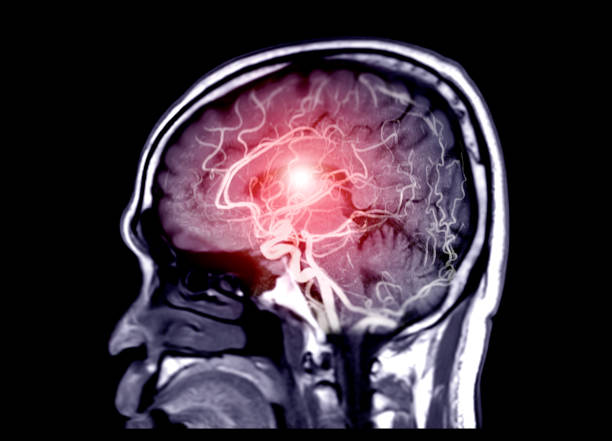

모야모야병 증상 제대로 알아보기

모야모야병은 중추신경계 질환 중 하나로, 이상한 소리와 자세, 신체적인 증상 등을 일으키는 질환입니다. 이 병은 실제로는 정신의학적인 질환으로 분류되며, 정확한 원인은 아직 알려지지 않았습니다. 하지만, 뇌의 신경전달물질인 도파민과 관련이 있을 수 있다는 가설이 제기되고 있습니다.

모야모야병의 특징은, 갑작스럽게 발생하는 이상한 소리와 자세, 그리고 다양한 신체적인 증상 등입니다. 환자는 자발적으로 특이한 소리나 움직임을 발생시키는 것이 아니라, 이것이 강제적으로 발생되기 때문에 어쩔 수 없이 소리를 내거나 움직임을 하게 됩니다. 이로 인해 일상생활에 큰 어려움을 겪을 수 있으며, 사회적인 이슈가 될 수도 있어 조기에 진단 후 치료를 받으셔야 합니다. 따라서 이번 시간에는 발생률이 높아지고 있는 모야모야병 증상에 대해 자세히 알아보겠습니다.